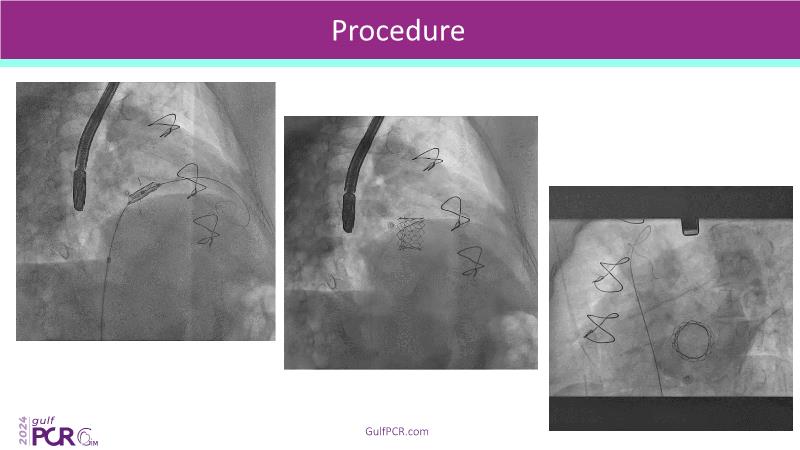

Stay ahead in TAVI innovation by exploring the advanced balloon-expandable Myval THV series. This session highlights the latest clinical data, optimal sizing and implantation techniques, and valuable real-world insights, including long-term follow-up results.

- To understand the best practices for Myval sizing and implantation technique for best outcomes

- To update on its experience and follow-up in "real-world" patient registries